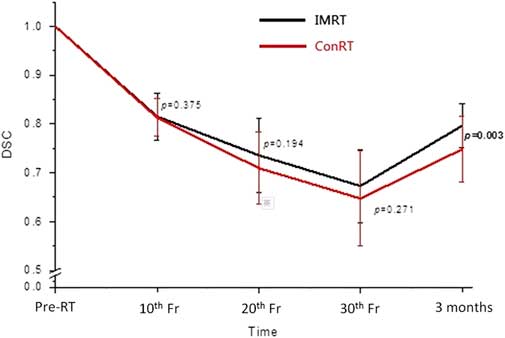

For the assessment of parotid gland changes, percentage change of volume (Δ%V) and dice similarity coefficient (DSC) were obtained. DSC, which indicated the spatial overlap between two volumes,Reference Zou, Warfield and Bharatha 14 was defined by (V o, V s)=2|V o∩V s| / |V o|+|V s|, where V o and V s were the volumes of original parotid gland and subsequent parotid gland at various time intervals, respectively, and ∩ was the intersection. A value of 1·0 would indicate perfect volume match between the two volumes, whereas 0 would imply no overlapping of volume. Translational displacements in x, y and z axes and total vector displacement (TVD), which was the three-dimensional displacement of the centroid, were obtained by comparing the parotid gland in each subsequent CT with that of the original planning CT using the MIM software. In addition to the parotid gland measurement, the change in lateral dimension of the patient’s head (ΔD L) was also measured which was an indication of the patient’s size. The lateral dimension of the patient’s head was defined as the width of the line perpendicular to the mid-line in the CT slice at level of the superior tip of the odontoid process (Figure 1).Reference Cao, Luo and Xu 15 The average values of each measured parameter for the ConRT and IMRT groups were calculated and compared. Normality test was conducted in each set of data. Independent t-test or Mann–Whitney test was conducted dependent on the normality of the data. All statistical tests were performed using Statistical Package for Social Science version 22 (IBM).

Figure 1 A transverse computed tomographic (CT) slice at the level of the tip of odontoid process showing the measurement of lateral dimension of the head.

The mean parotid volume in both groups decreased with a maximum reduction of 35% at the 30th fraction (Figure 3). There were no significant differences between the ConRT and IMRT groups from 10th to 30th fractions. Volume recovery was observed in both groups at 3 months following RT with significantly greater recovery in the IMRT group (p=0·007). The trend of DSC was similar to that of the volume change. It decreased from pre-treatment to 30th fraction and partially recovered at 3 months after treatment (Figure 4). Significant difference between ConRT and IMRT was only noted at the 3 months post-RT interval with the IMRT group demonstrating a better restoration of the original shape (p=0·003).

Figure 4 Comparison of the mean dice similarity coefficients (DSC) of parotid glands between conventional radiotherapy (ConRT) and intensity-modulated radiotherapy (IMRT) plans over the radiotherapy course up to 3 months after treatment. Note: The horizontal lines indicate the error bars.

With regard to the geometric changes of the parotid gland during radiotherapy, our study demonstrated that there were no significant differences between patients treated by ConRT and IMRT. For both groups of patients, the parotid gland demonstrated continuous shrinkage and medial migration during the treatment course. They were reflected by the increase of Δ%V, DSC and TVD from pre-treatment to 30th fraction, respectively. The shrinkage of parotid glands during radiotherapy has been reported in previous studiesReference Barker, Garden and Ang 16 , Reference Zhang, Lin and Wu 17 and it was mainly caused by the loss of gland parenchyma and acinar cell atrophy due to high dose radiation.Reference Radfar and Sirois 18 , Reference Wang, Yan and Zhang 19 The volume reduction of the parotid gland subsequently changed its shape and therefore resulted in a similar trend in DSC as for Δ%V. This medial migration of the parotid gland during radiotherapy was caused by the shrinkage of radiosensitive NP tumour, which was situated medially to the parotid gland and created space for the parotid gland to move in. Another associated factor could be due to the weight loss of the patients, whose head size became smaller leading to the lateral structures moved closer to the mid-plane. Actually such medial movement of the parotid gland during radiotherapy course has been reported by some studies.Reference Fung, Wu and Teo 20 , Reference Barker, Garden and Ang 21 Our study has shown that NPC patients generally had gradual weight loss during a course of radiotherapy. This was reflected by the reduction of the lateral head dimension. The phenomenon of weight lost, however, may vary across other institutions depending on nutritional support given. This is a common phenomenon for head and neck cancer patients as a result of poorer nutritional status due to radiation induced oral mucositis and xerostomia. The effect would be compounded with concurrent chemotherapy, which is commonly applied for stage II disease or above for NPC patients.